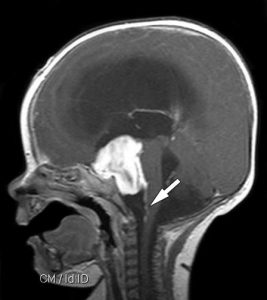

Cura instantânea de tumor cerebral em Medjugorje